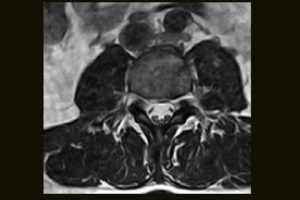

Clinical Images

Immediate access to high quality MR images can help your practice achieve new levels of efficiency and patient satisfaction. From C-spine anomalies to foot injuries, the S-scan dedicated MRI system efficiently delivers a range of MSK MRI studies within your existing practice.

Comprehensive MSK Imaging